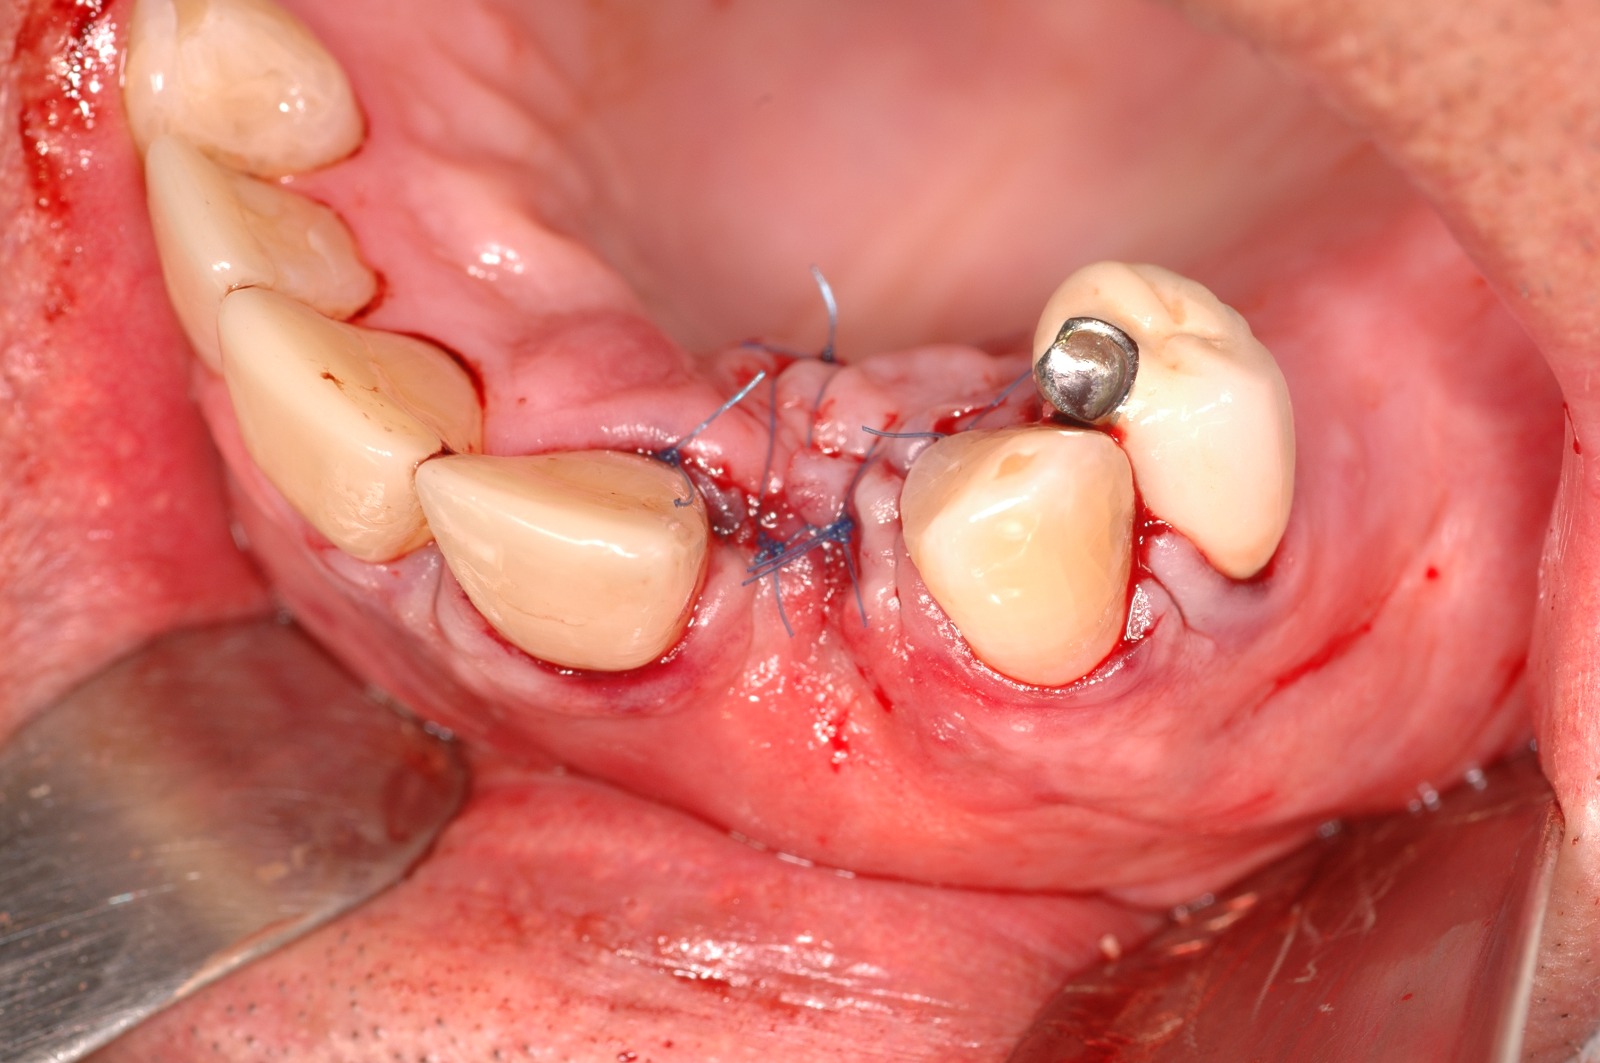

Regeneración ósea guiada

En algunos casos, puede ser necesario realizar un injerto óseo antes o durante la colocación de los implantes dentales. Esto se debe a que la cantidad o calidad del hueso puede no ser suficiente para soportar el implante de manera adecuada.

Casos Clínicos

Observa cómo la ciencia y la tecnología se unen para reconstruir el hueso perdido y devolver la confianza a quien la había perdido